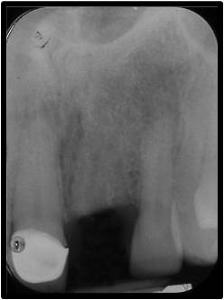

Pre-op and Post-op of implant placed at #9

Before

After